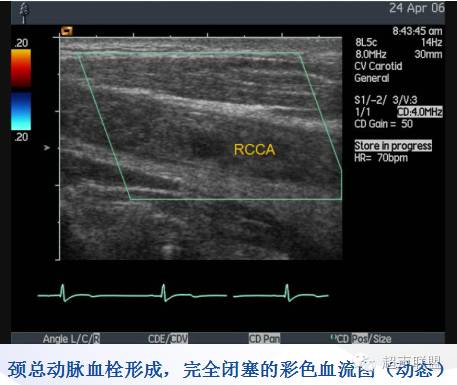

(3)管腔内血栓形成:急性期血栓为低回声,以后回声逐渐增强。

完全闭塞 | 2DE见不到管腔, CDFI无血流信号 | 探不到血流信号 | 无 | 无 |